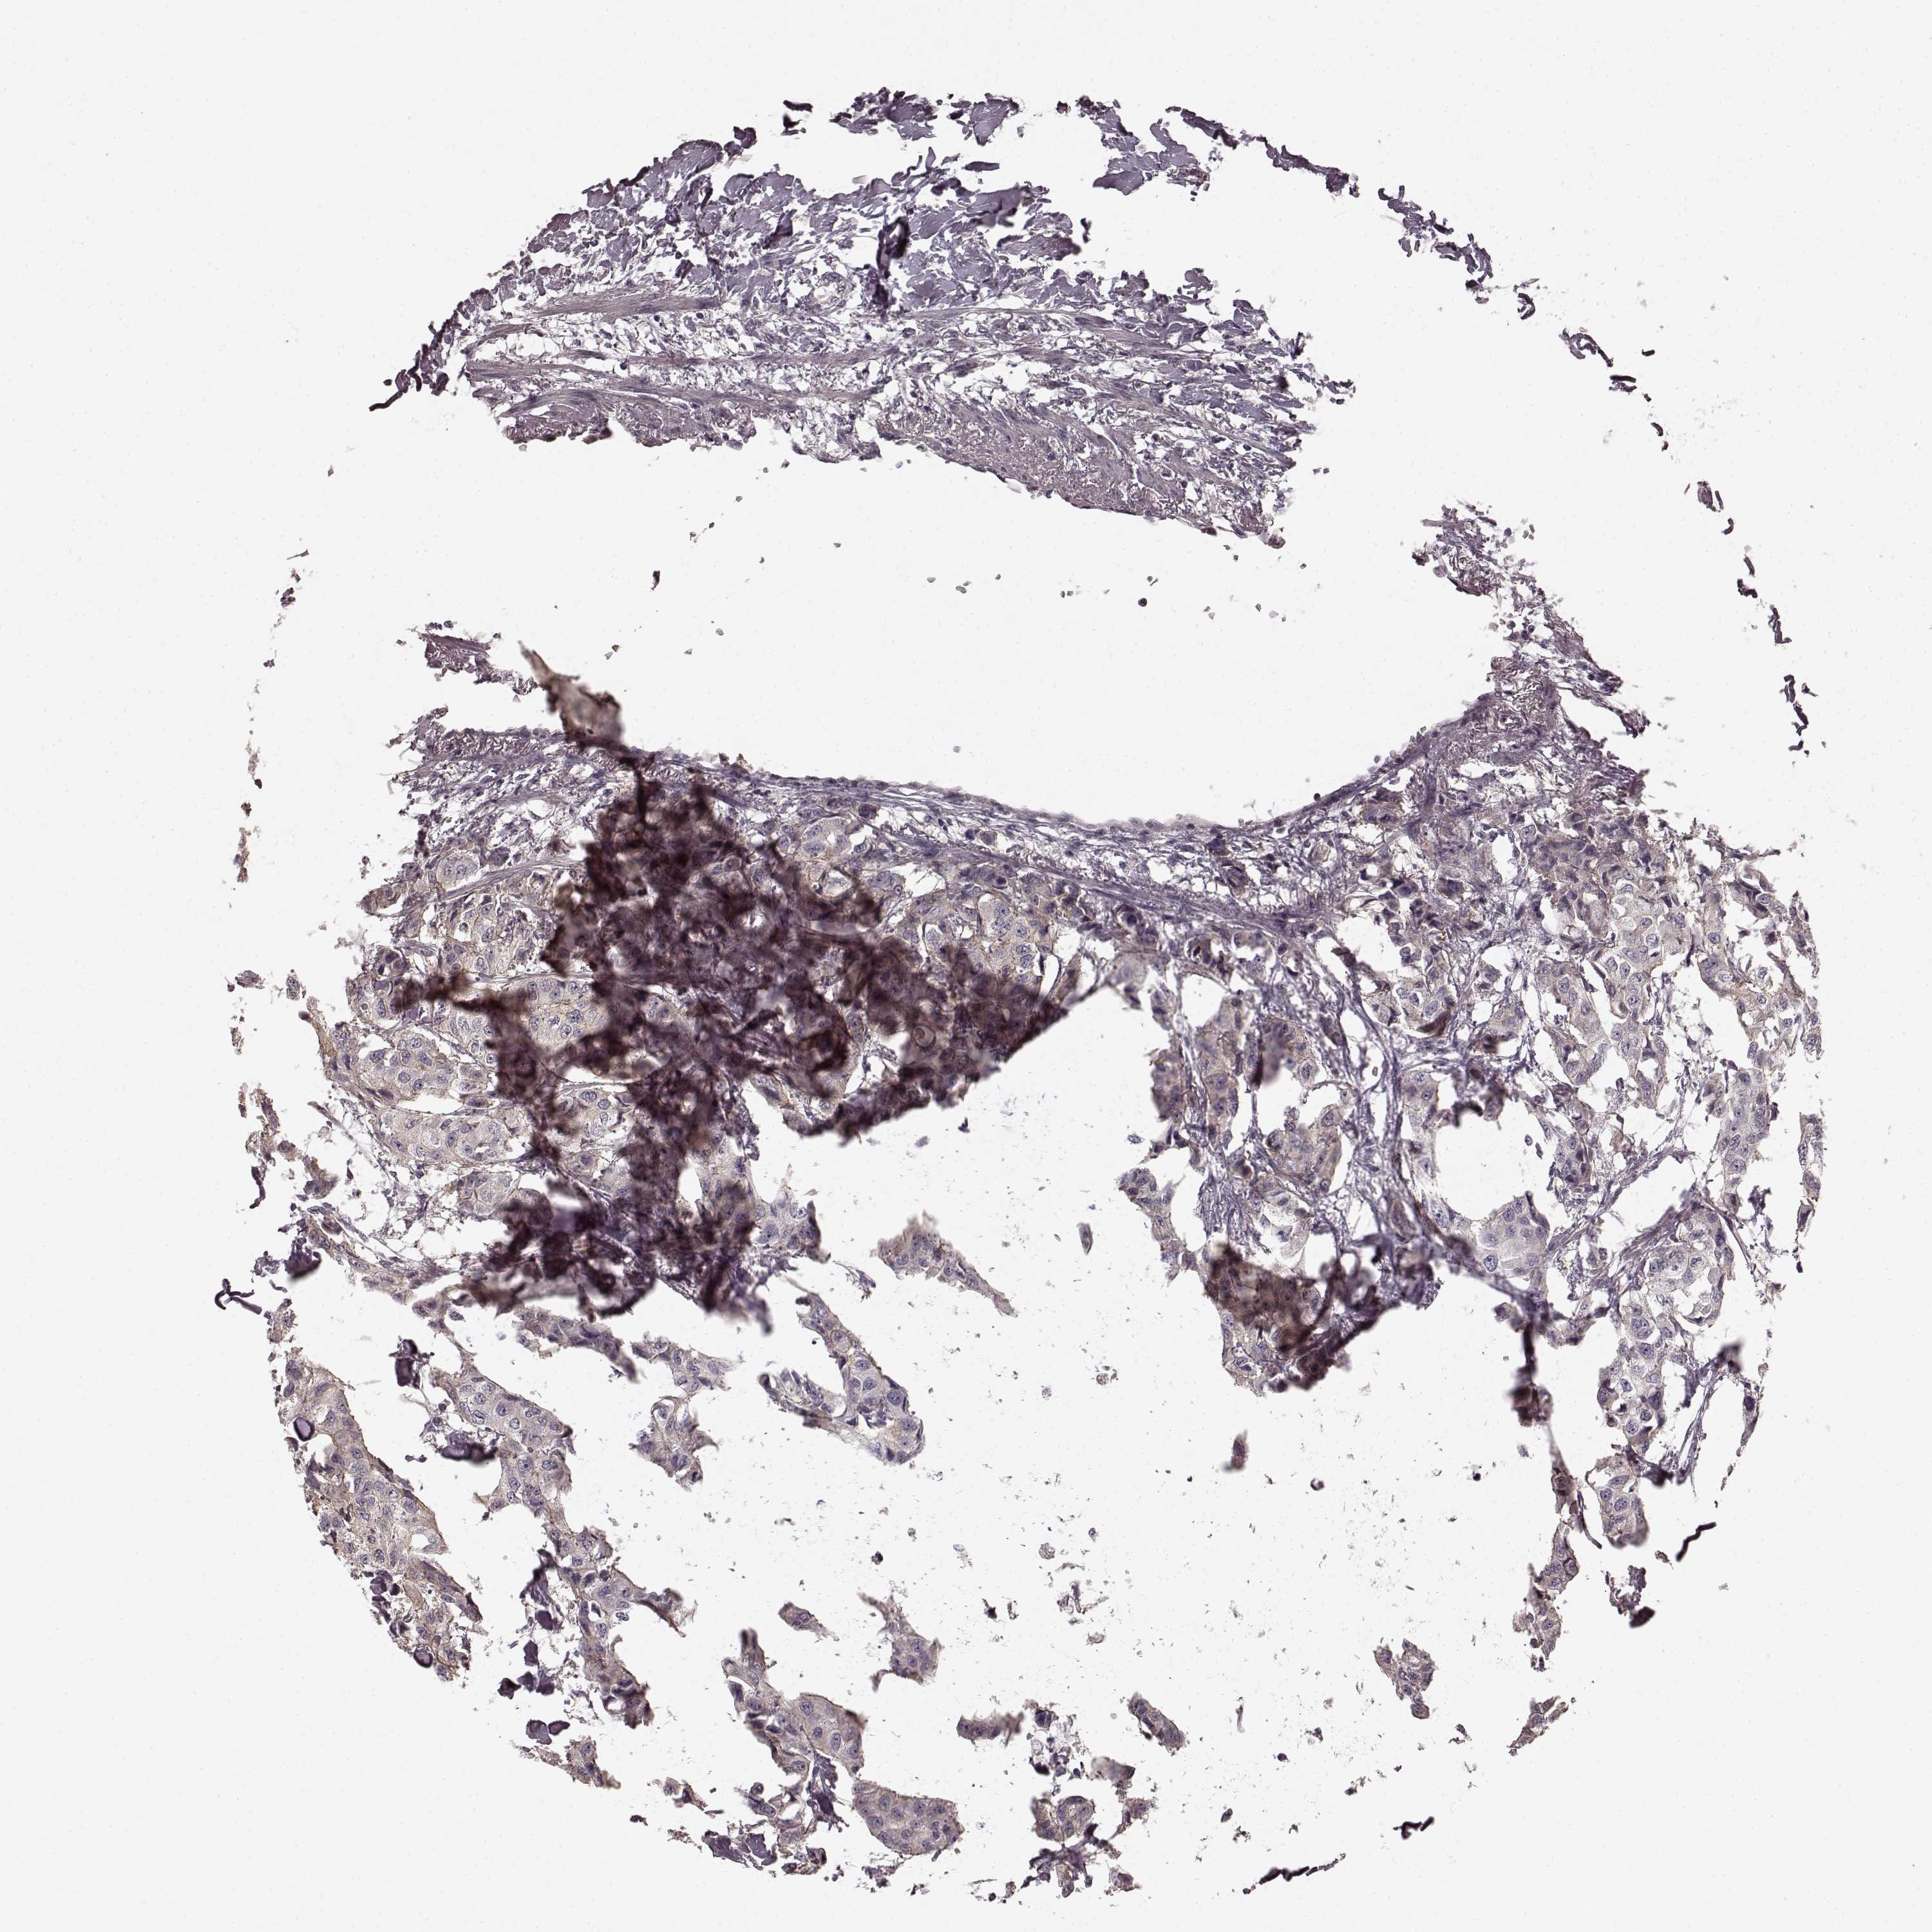

CANCER BREAST CANCER Show tissue menu

BRCA TCGA BRCA VALIDATION PROTEIN EXPRESSION

ANTIBODIES

AND

VALIDATION